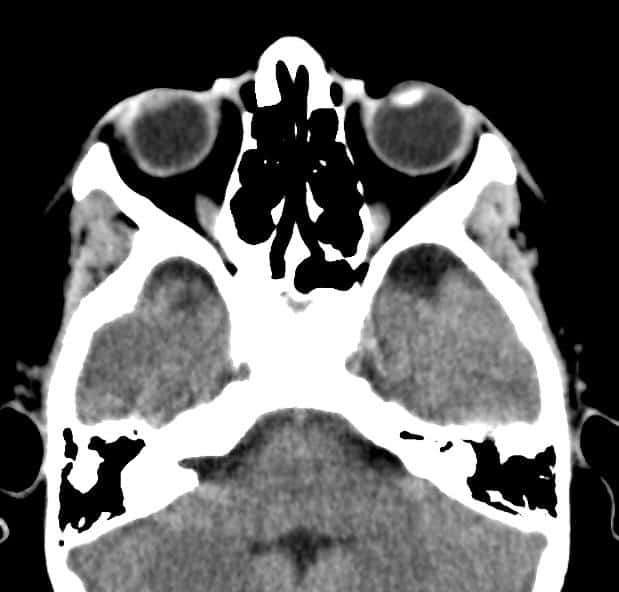

Đục thủy tinh thể trái

Chấn thương nhãn cầu - Ảnh 4

Chấn thương nhãn cầu

» Thông tin: Nam giới – 10 tuổi.

» Lâm sàng: Mù mắt phải sau chấn thương.

# Thủy tinh thể phải giảm tỷ trọng do phù nề.